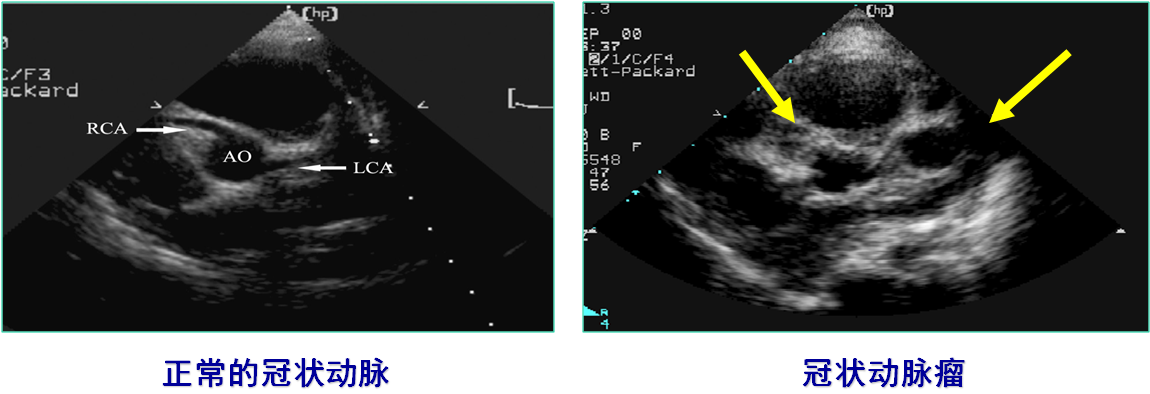

Echocardiography,ECHO (超声心动图)

CoronaryAngiography (冠状动脉造影)

左、右冠状动脉巨大冠脉瘤伴血栓形成

左前降支巨大冠脉瘤内有血栓,远端狭窄

回旋支冠脉瘤

右冠脉巨大冠脉瘤伴狭窄

冠状动脉损害:冠状动脉扩张(coronary artery dilation)

冠状动脉瘤(coronary artery aneurysms)

冠状动脉狭窄(coronary artery stenosis)